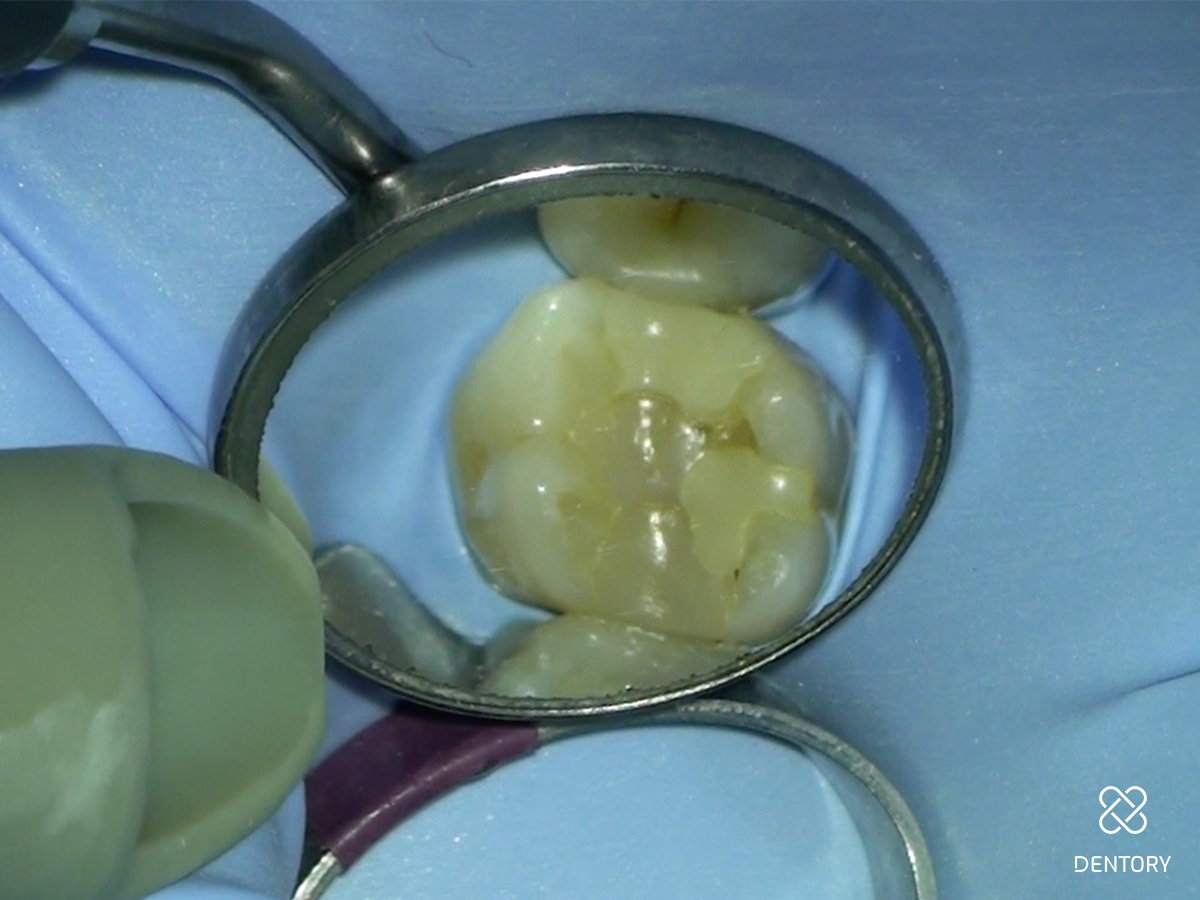

Abbildung 1

Klinische Ausgangssituation.